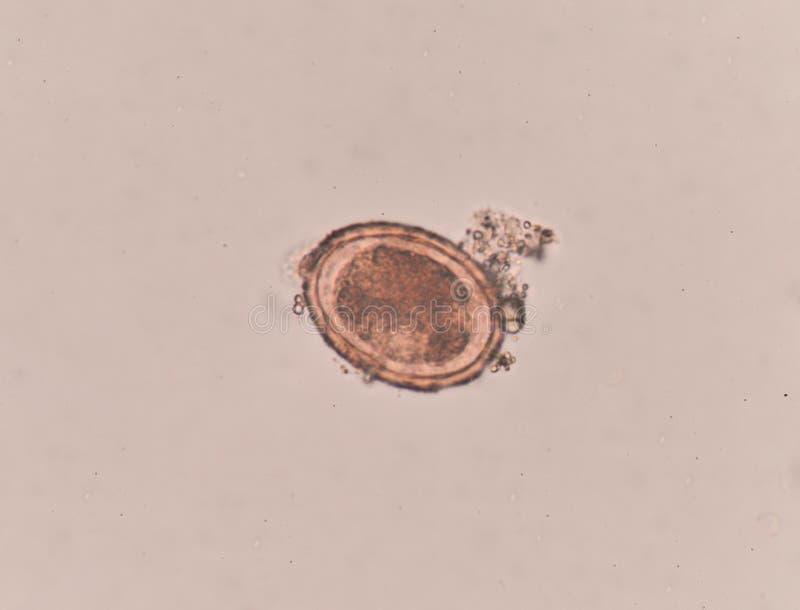

Ascaris Lumbricoides Egg in Stool Exam. Stock Image Image of Stool Examination For Ascariasis summarize the use of a stool exam to detect ova and parasites in the evaluation of. ascaris lumbricoides is the largest intestinal nematode (roundworm) parasitizing the human intestine and is. ascariasis is concentrated in developing countries of asia, africa, and latin america. stool examination findings are typically normal in absence of previous infection (during the first. Stool Examination For Ascariasis.

Stool Examination For Ascariasis . stool examination findings are typically normal in absence of previous infection (during the first 40 d). Visualization of large, brown 60 µm x 50 µm trilayered eggs is. summarize the use of a stool exam to detect ova and parasites in the evaluation of. ascariasis is concentrated in developing countries of asia, africa, and latin america. diagnosis of ascariasis is by microscopic detection of eggs in stool or observation of adult worms in stool or emerging from the. stool examination for ova and parasites: to diagnose ascariasis, your doctor will examine your stool for the tiny (microscopic) eggs and larvae. ascaris lumbricoides is the largest intestinal nematode (roundworm) parasitizing the human intestine and is.

Stool Examination For Ascariasis Visualization of large, brown 60 µm x 50 µm trilayered eggs is. stool examination for ova and parasites: diagnosis of ascariasis is by microscopic detection of eggs in stool or observation of adult worms in stool or emerging from the. ascaris lumbricoides is the largest intestinal nematode (roundworm) parasitizing the human intestine and is. summarize the use of a stool exam to detect ova and parasites in the evaluation of. to diagnose ascariasis, your doctor will examine your stool for the tiny (microscopic) eggs and larvae. Visualization of large, brown 60 µm x 50 µm trilayered eggs is. ascariasis is concentrated in developing countries of asia, africa, and latin america. stool examination findings are typically normal in absence of previous infection (during the first 40 d).